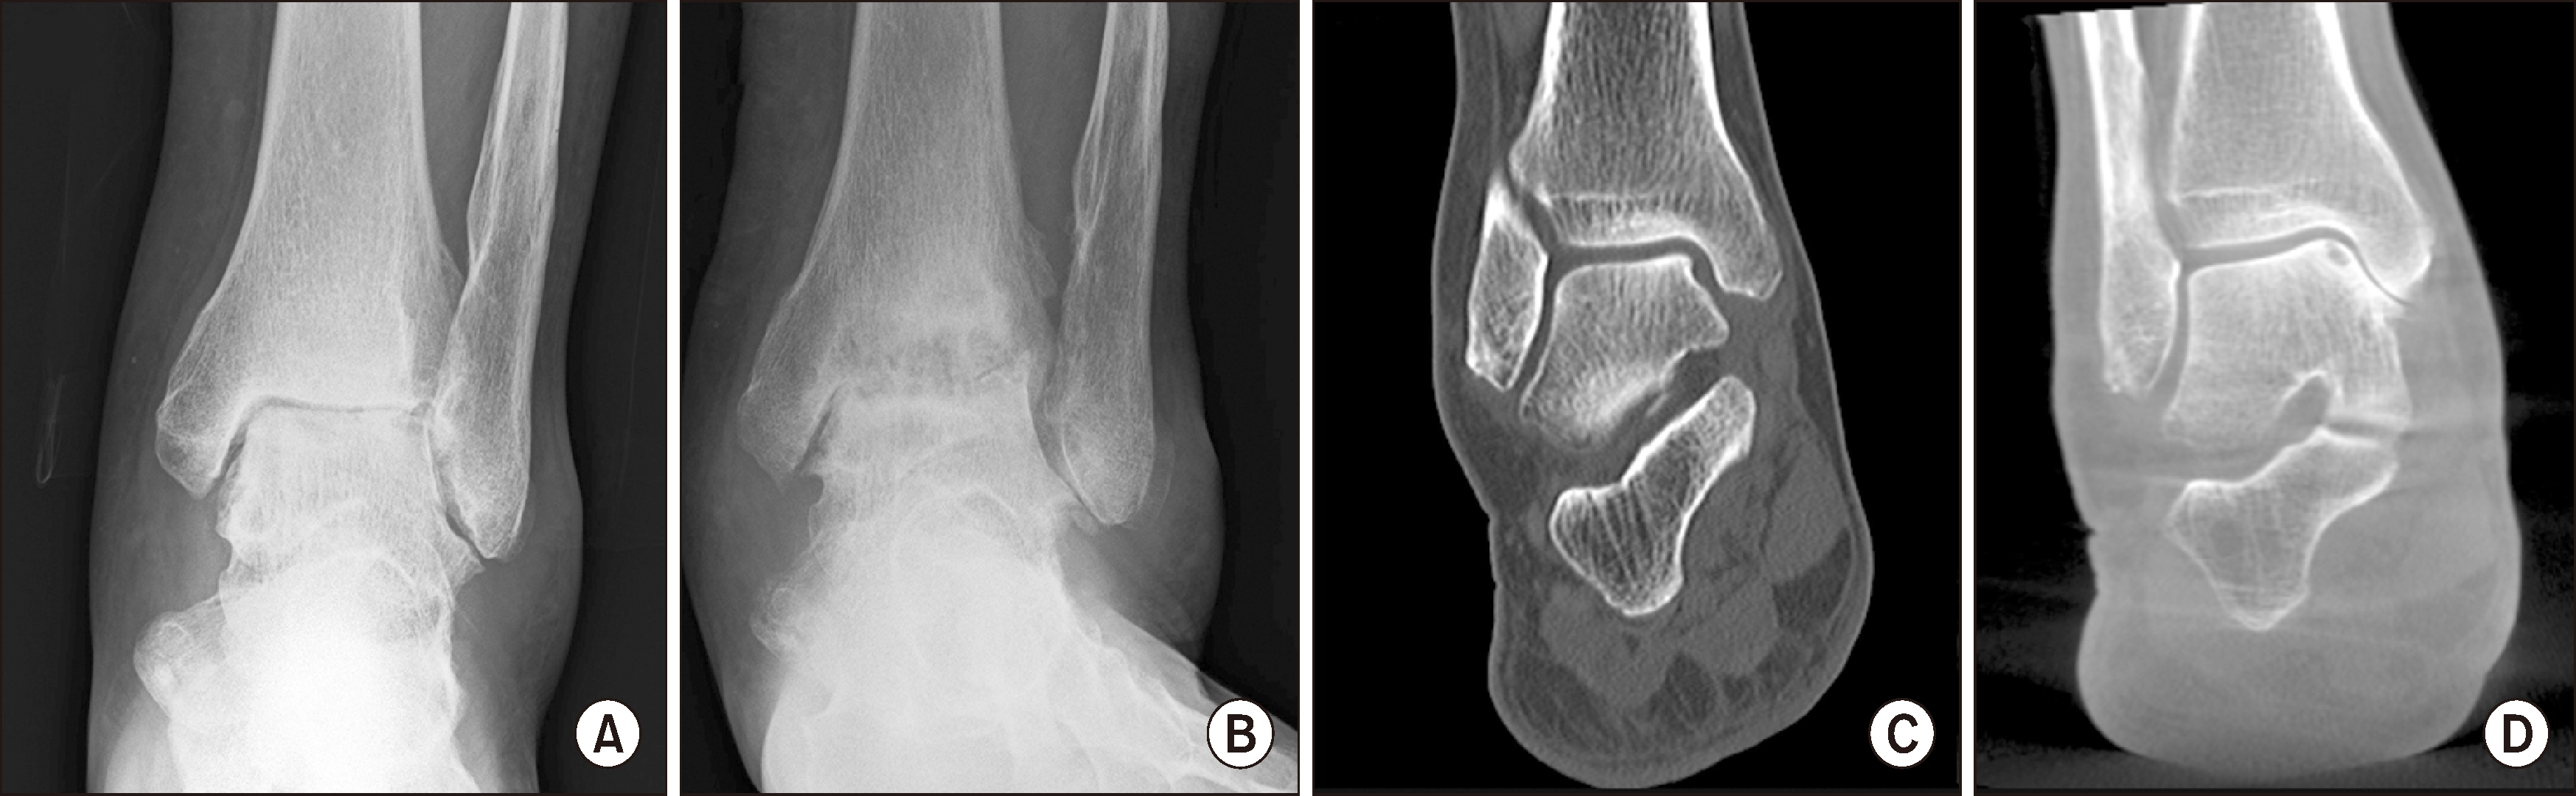

이에 WBCT를 활용한 새로운 발목 관절염 분류법이 제안되었는데, Richter 등12)은 WBCT 영상을 기반으로 발목 관절염을 4단계로 세분화하였다. 1단계는 관절 간격이 완전히 소실되지 않고 골극이 형성된 상태이며, 2단계는 부분적 또는 전체적인 관절 간격 소실을 보이는 상태로 정의하였다. 3단계에서는 관절면의 상합(congruence)은 유지된 상태로 연골하 낭종(subchondral cyst)이 존재하는 반면에, 4단계는 관절면의 불상합(incongruence)과 함께 관절 파괴가 진행된 상태로 정의하였다(Fig. 4). 이러한 새로운 분류법은 관절염의 기본적인 특징인 관절 간격 감소, 골극 형성, 연골하 낭종을 고려하였다는 장점이 강조된다. 또한, Tazegul 등13)은 WBCT 영상에서 Hounsfield 단위를 활용하여 발목 관절염을 정량적으로 평가하는 방법을 개발하였다. 관절 내 특정 부위를 네 개의 부위로 나누고, 각 부위의 Hounsfield 단위를 기반으로 관절 간격 및 연골 변화가 일어나는 부위를 보다 객관적으로 분석할 수 있었다. 비록 해당 연구는 소규모 샘플을 대상으로 시행한 방법론적 제안에 불과하지만, 향후 WBCT를 이용한 정량적 분석이 발목 관절염 분류의 신뢰성과 재현성을 향상하는 데 기여할 가능성이 크다.

Figure 4

Ankle arthritis classification system by weight-bearing computed tomography. (A) First degree of osteoarthritis with osteophyte formation and joint space narrowing, but not complete loss. (B) Second degree of osteoarthritis with partial or complete loss of joint space. (C) Third degree of osteoarthritis with additional subchondral cysts, with remaining joint surface congruency. (D) Fourth degree of osteoarthritis with aggravated joint surface destruction and incongruence.